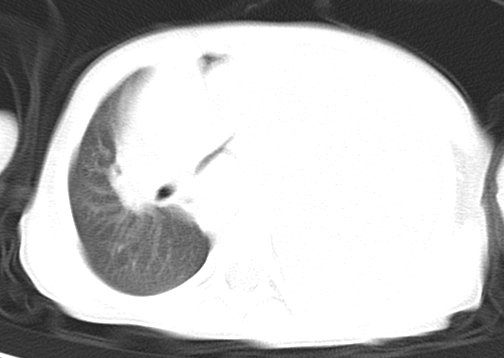

患儿 女 4岁,发热 咳嗽 胸透 考虑:左侧脓胸

左侧胸廓内见大量密实阴影,肺尖部尚有少量肺组织影,纵膈明显受压移位,肋骨未见明显受侵征象,虽然病人年龄较小,但如此大量的“积液”,还是要警惕,不同意一般感染,可结合穿刺脱落细胞学检查。

1)考虑左肺炎症感染。2)左侧大量胸腔积液。

1)考虑左肺炎症感染。2)未经穿刺只能定左侧大量胸腔积液。

左侧张力性大量胸腔积液压迫性肺不张、感染;建议治疗后复查。